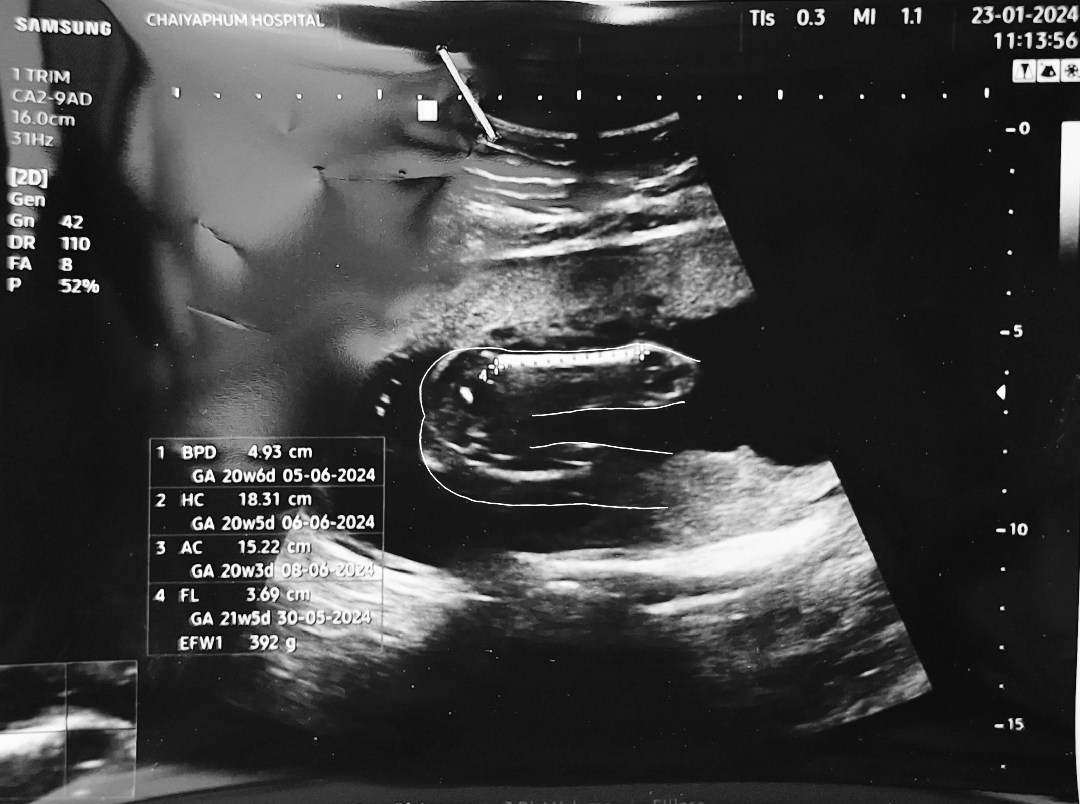

ลูกสาวเเน่นอนจ้าคุณพ่อ น้องไม่ได้หนีบขาด้วยค่ะ ถ้าผช.จะมีจู๋โผล่ค่ะ

แบบนี้ได้ลูกสาวหรือลูกชายครับ

รูปซาวด์ออกมาเเบบนี้ผญ.หรือผช.ครับ

ลูกสาวไหมคะ ของเราลูกชายจะมีจุดขาวๆขึ้นตรงหว่างขาด้วย